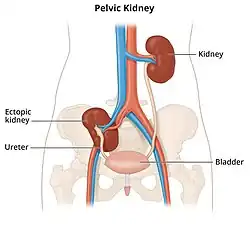

Diagram showing a pelvic ectopic kidney - Thoracic: kidney that protrudes through the diaphragm into the posterior mediastinum. An intrathoracic kidney could be a "real" ectopic kidney without any diaphragm abnormalities or can be related to diaphragmatic hernias or traumatic diaphragm ruptures.[4]

- Pelvic: kidney that fails to ascend and remains in the pelvic brim, below the level of aortic bifurcation.[5]